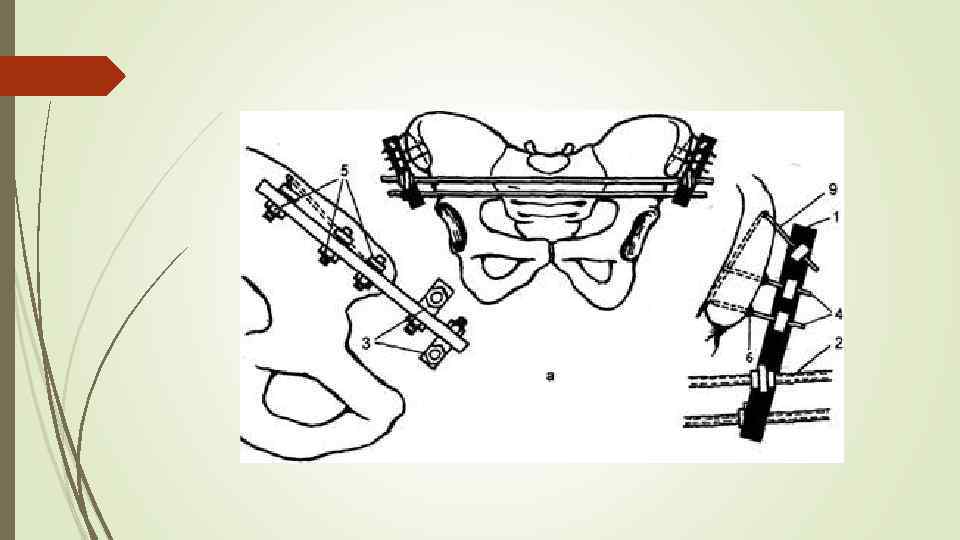

Принципы укладки в зависимости от месторасположения перелома 1. При разрыве лонного сочленения и переднего полукольца – больной укладывается в гамак, подвешенный за Балканскую раму